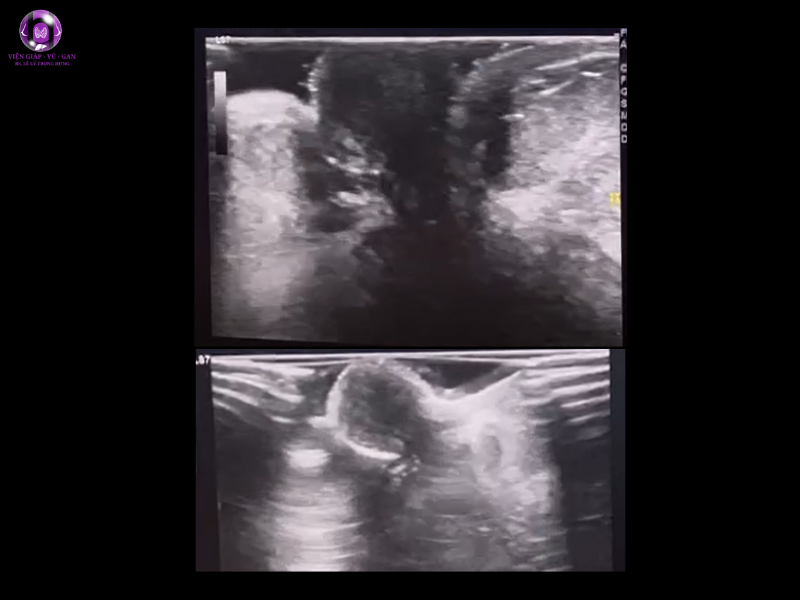

- Tham khảo kết quả nhũ ảnh của BV:

- Sau núm vú trái có vùng xáo trộn cấu trúc 29x45mm ( BIRADS 4)